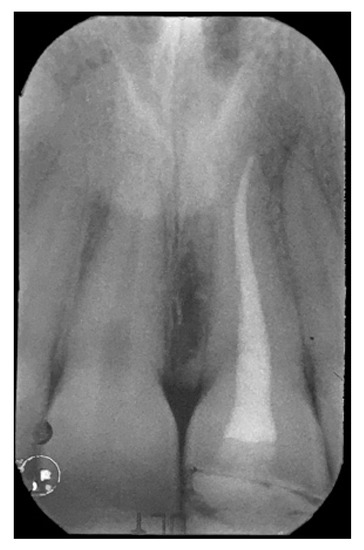

2. Case Presentation